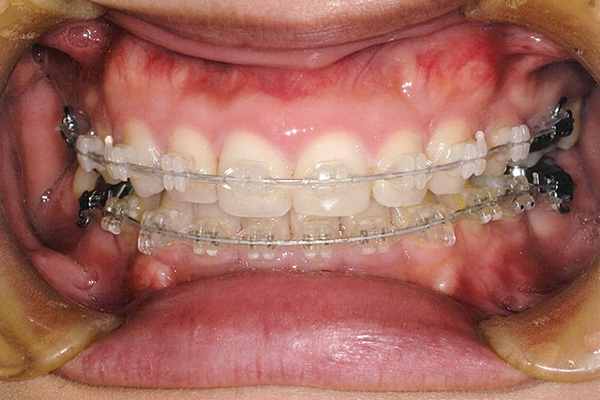

20代 女性

| 症状 | 下顎第一大臼歯の欠損 |

治療経過

3ヶ月後